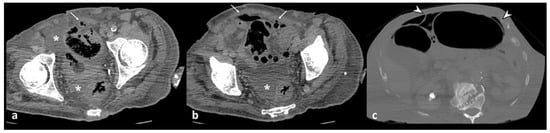

Figure 3. Axial unenhanced (a), axial and coronal contrast-enhanced CT images (b,c) show wall thickening of the left colon and inflammatory mass, without walls, located near the inflamed colonic tract, oval in shape, without an enhancing wall, that represents a peridiverticular phlegmon (arrowheads).

An increased density of pericolic fat [fat stranding] and a small amount of pericolic fluid represent the main mesenteric findings, which, combined with the mural thickening, suggest a localized inflammatory process in uncomplicated diverticulitis (Figure 2) [10,12,13]. The degree of fat stranding can range from “dirty fat” to peridiverticular phlegmon. The phlegmon consists of an inflammatory mass, without walls, located near the inflamed colonic tract, round or oval in shape, and on CT, it presents with high attenuation compared to the mesenteric fat, without an enhancing wall (Figure 3) [3,5]. Multiplanar reconstruction allows for identifying minimum amounts of pericolic fat stranding in the case of horizontal colonic segments [12]. Pereira et al. suggest that the presence of “disproportionate” fat stranding concerning mural thickening suggests the diagnosis of diverticulitis [21]. A small amount of fluid on the root of the mesentery [comma sign] and thickening of the lateroconal fascia are additional signs of an inflammatory process (Figure 1) [13].